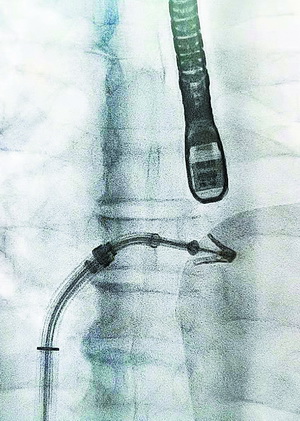

微创经股静脉送入夹合器。

4月10日上午,何大爷的手术在厦心杂交手术室进行。手术全程都在跳动的心脏上完成,厦心院长王焱教授率团队将一个特制的夹合器经股静脉送入、穿刺房间隔、进入左心房,在食道超声及X 线引导下,使用夹合器夹住二尖瓣前、后瓣返流严重部位,如同订书机装订一般,使二尖瓣在收缩期由大的单孔变成小的双孔,缩小瓣口面积,从而减少二尖瓣返流,让二尖瓣恢复正确的打开和关闭效果。这一超微创手术持续了3个多小时,术后超声评估显示患者二尖瓣返流基本消失。这也是我省开展的第一例经导管二尖瓣钳夹术。